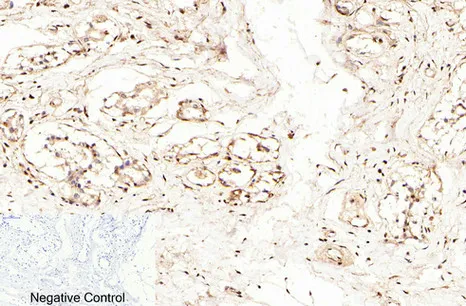

E-Selectin Rabbit Polyclonal Antibody

Cat: APRab10626

Endoglin Rabbit Polyclonal Antibody

Cat: APRab10463